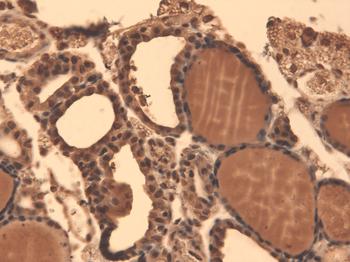

应用稀释比例:WB (1:1000), IHC (1:1000)

应用注释:1 µg/ml of SMC-391 was sufficient for detection of hNIS in 20 µg of transfected COS-7 cell membrane lysate by ECL immunoblot analysis using Goat anti-mouse IgG:HRP as the secondary antibody.